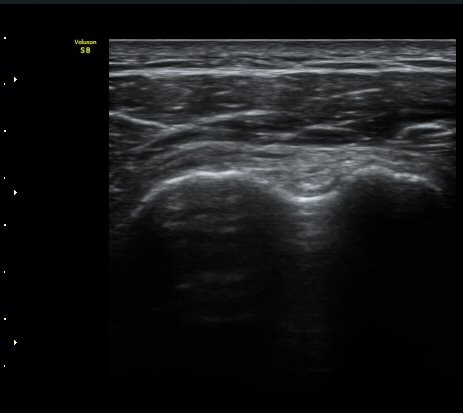

ÀÌµÎ¹Ú±Ù°Ç È¾´Ü¸é°Ë»ç¿¡¼­ ƯÀÌ ¼Ò°ßÀ» º¸ÀÌÁö ¾ÊÀ½(»çÁø 1, 2).